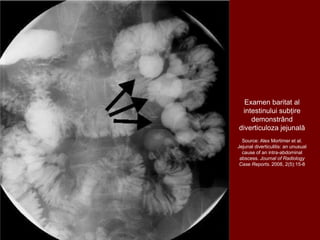

Examen baritat al

intestinului subțire

demonstrând

diverticuloza jejunală

Source: Alex Mortimer et al.

Jejunal diverticulitis: an unusual

cause of an intra-abdominal

abscess. Journal of Radiology

Case Reports. 2008, 2(5):15-8